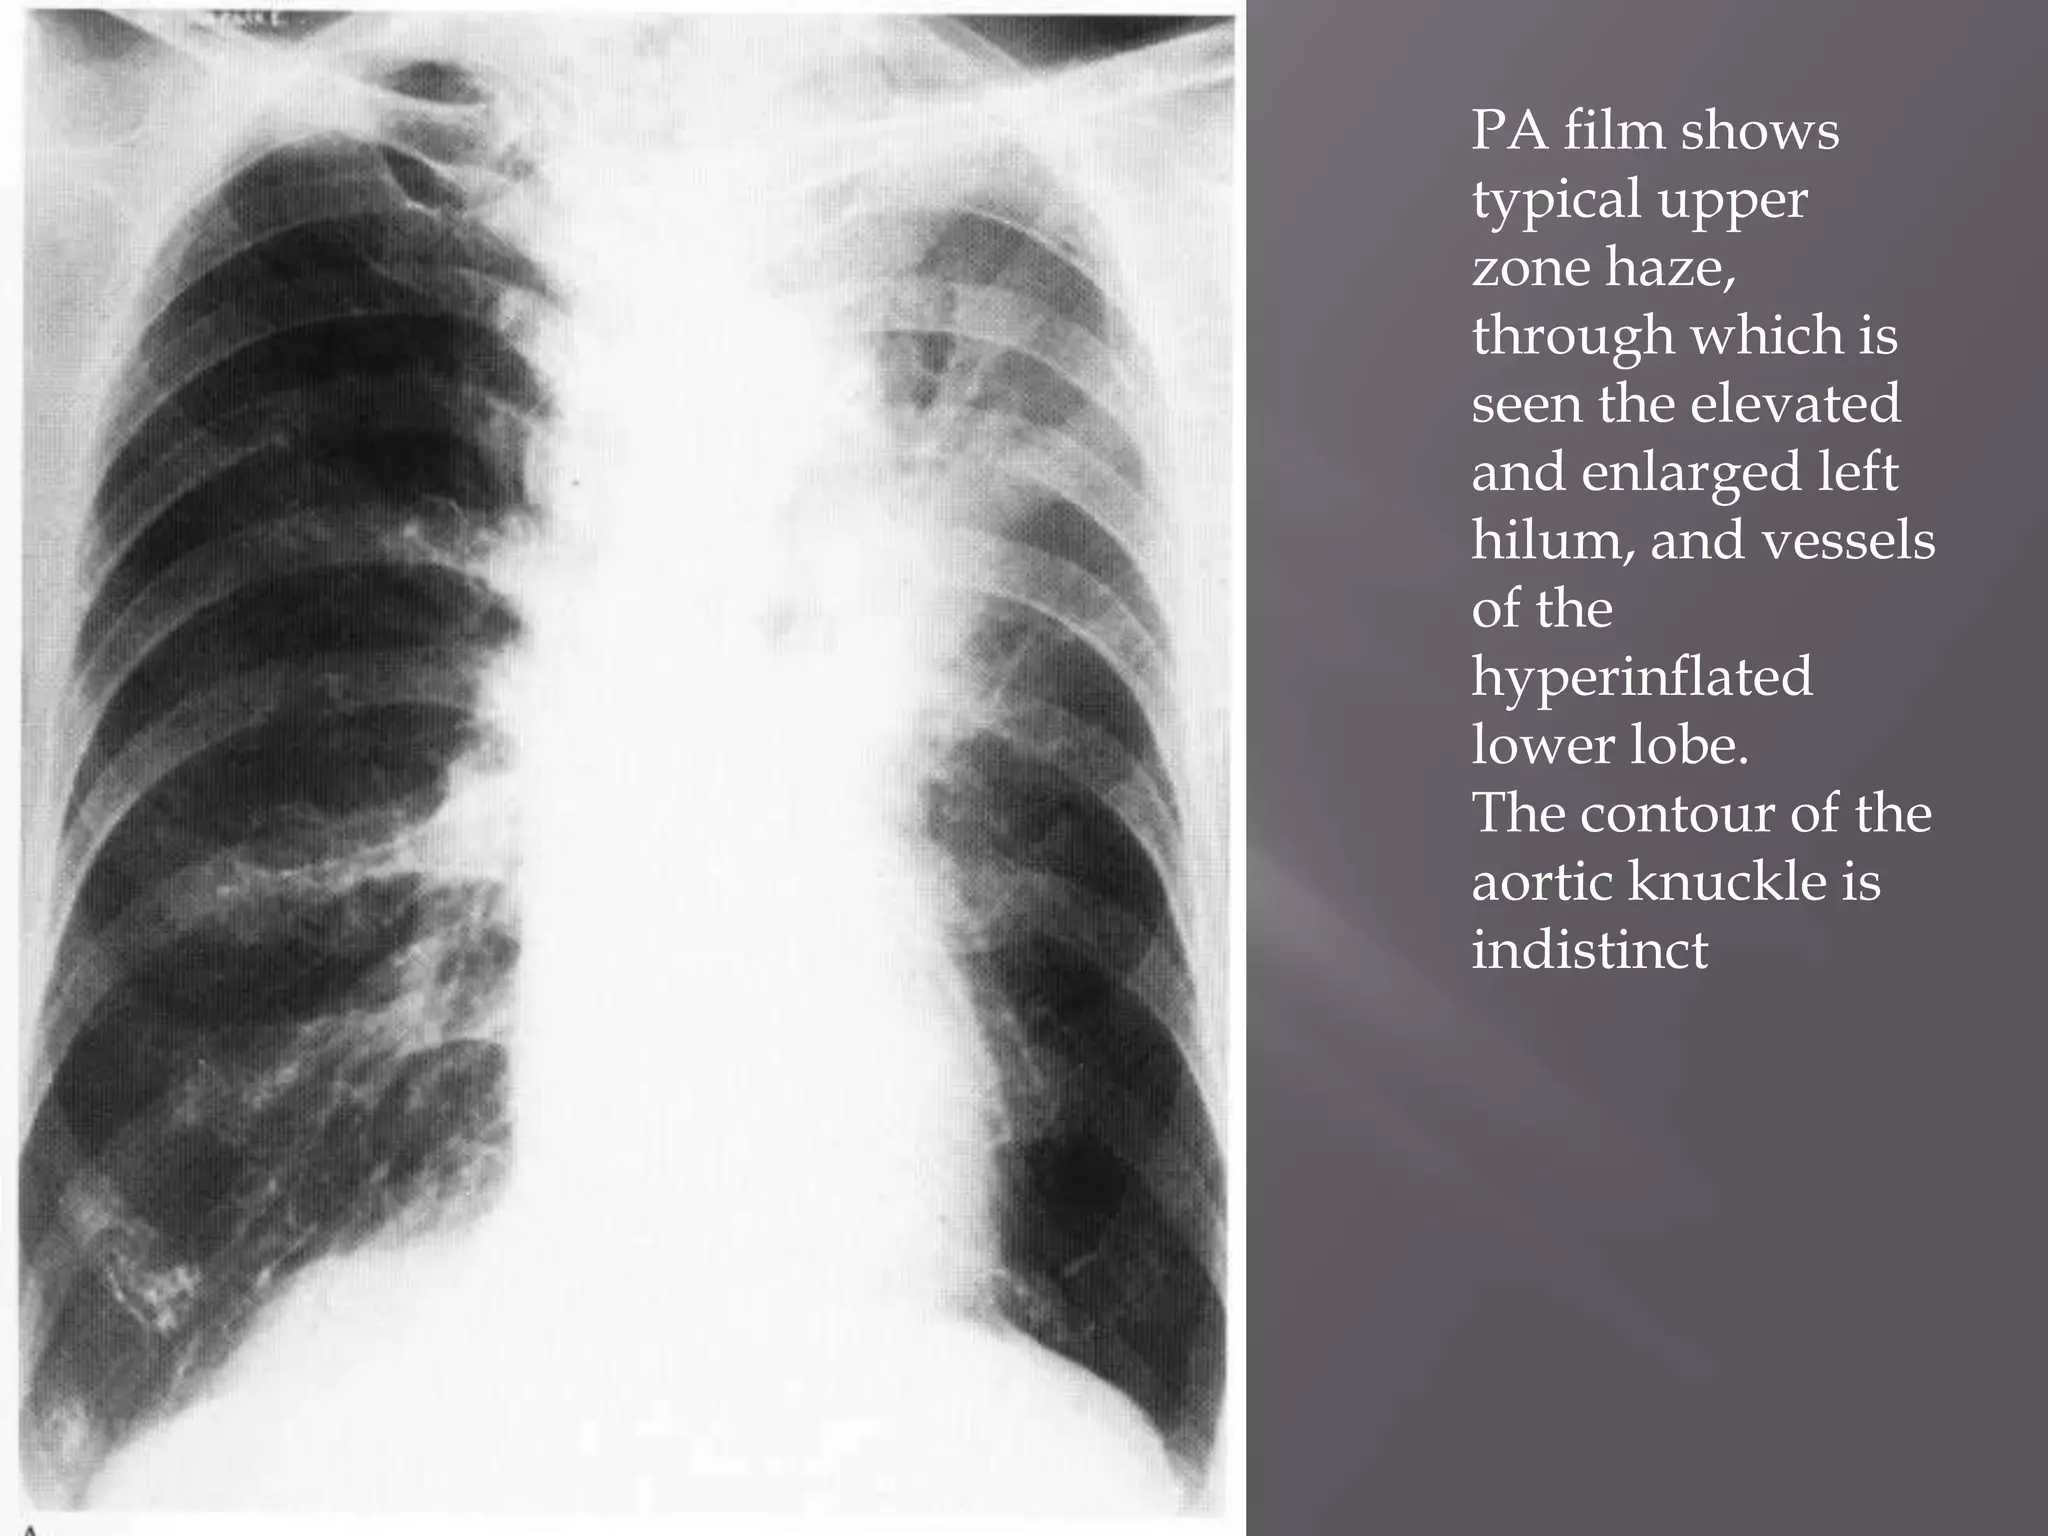

PA film shows

typical upper

zone haze,

through which is

seen the elevated

and enlarged left

hilum, and vessels

of the

hyperinflated

lower lobe.

The contour of the

aortic knuckle is

indistinct

. PA film shows typicalupper zone haze, through which is seen the elevated and enlarged left hilum, and vessels of the hyperinflated lower lobe. The contour of the aortic knuckle is indistinct